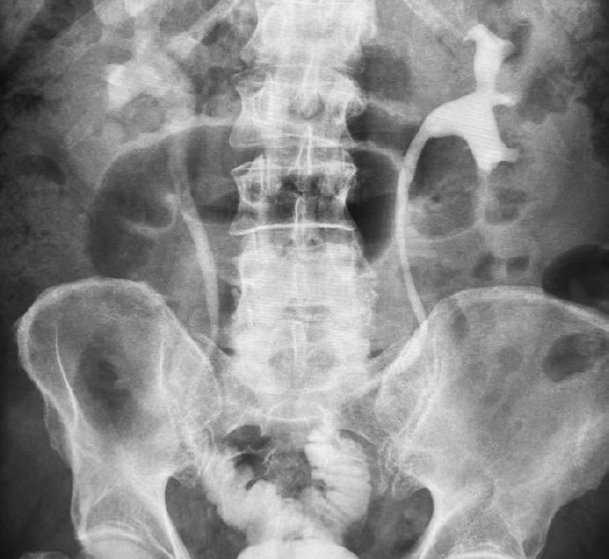

Fig. 8. Bilateral U-shaped ileoureteroplasty

Fig. 9. Excretory ureterogram one year after laparoscopic bilateral U-shaped ileoureteroplasty. The function of the kidneys and newly created urinary tract is normal